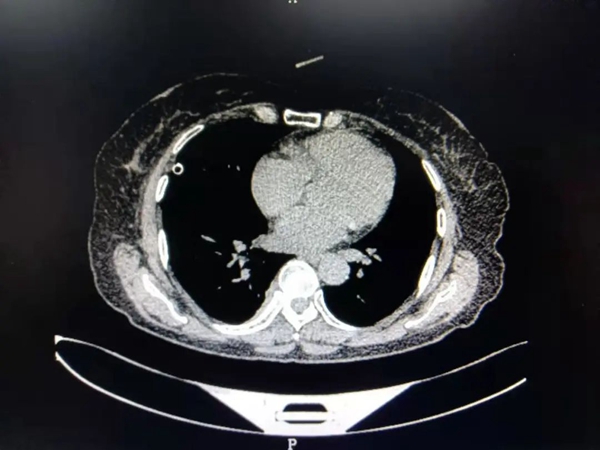

患者陈女士,59岁,因右侧胸背部疼痛半个月来我院就诊,经检查,胸部Ct结果显示:T8椎体旁紧贴胸膜处占位病变,且气管有先天畸形改变。陈女士既往有冠心病、高血压病和甲亢病史,家庭贫困。考虑其家庭状况,经充分术前评估,主管医生葛庆升详细告知陈女士病情及诊疗方案后,陈女士及其家属反复思量要求在家乡医院进行手术治疗。在郑州大学第二附属医院苏彦河教授的技术指导下,胸外科团队制定了周密的诊疗方案,因无法为陈女士完成单肺呼吸麻醉,经麻醉科会诊后,决定对其施行人工气胸胸右侧胸腔镜下纵膈肿瘤切除术,人工制造气胸,在纵膈中自下向上极度精准的操作,切除肿瘤。手术过程十分顺利,术中几乎无出血,术后患者恢复良好,现已康复出院。

![]() ![]() (术后CT) | ||